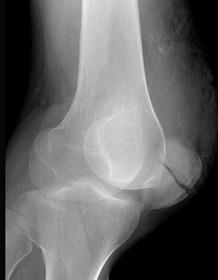

问题 21岁男性,在赛跑途中突然闻及左膝撕裂声,然后倒地,入院查体左膝不能主动伸直,X线片如图所示,造成骨折的原因是 ( )

选项 A、直接暴力 B、肌肉拉力 C、病理性骨折 D、间接暴力 E、积累性劳损

答案 B